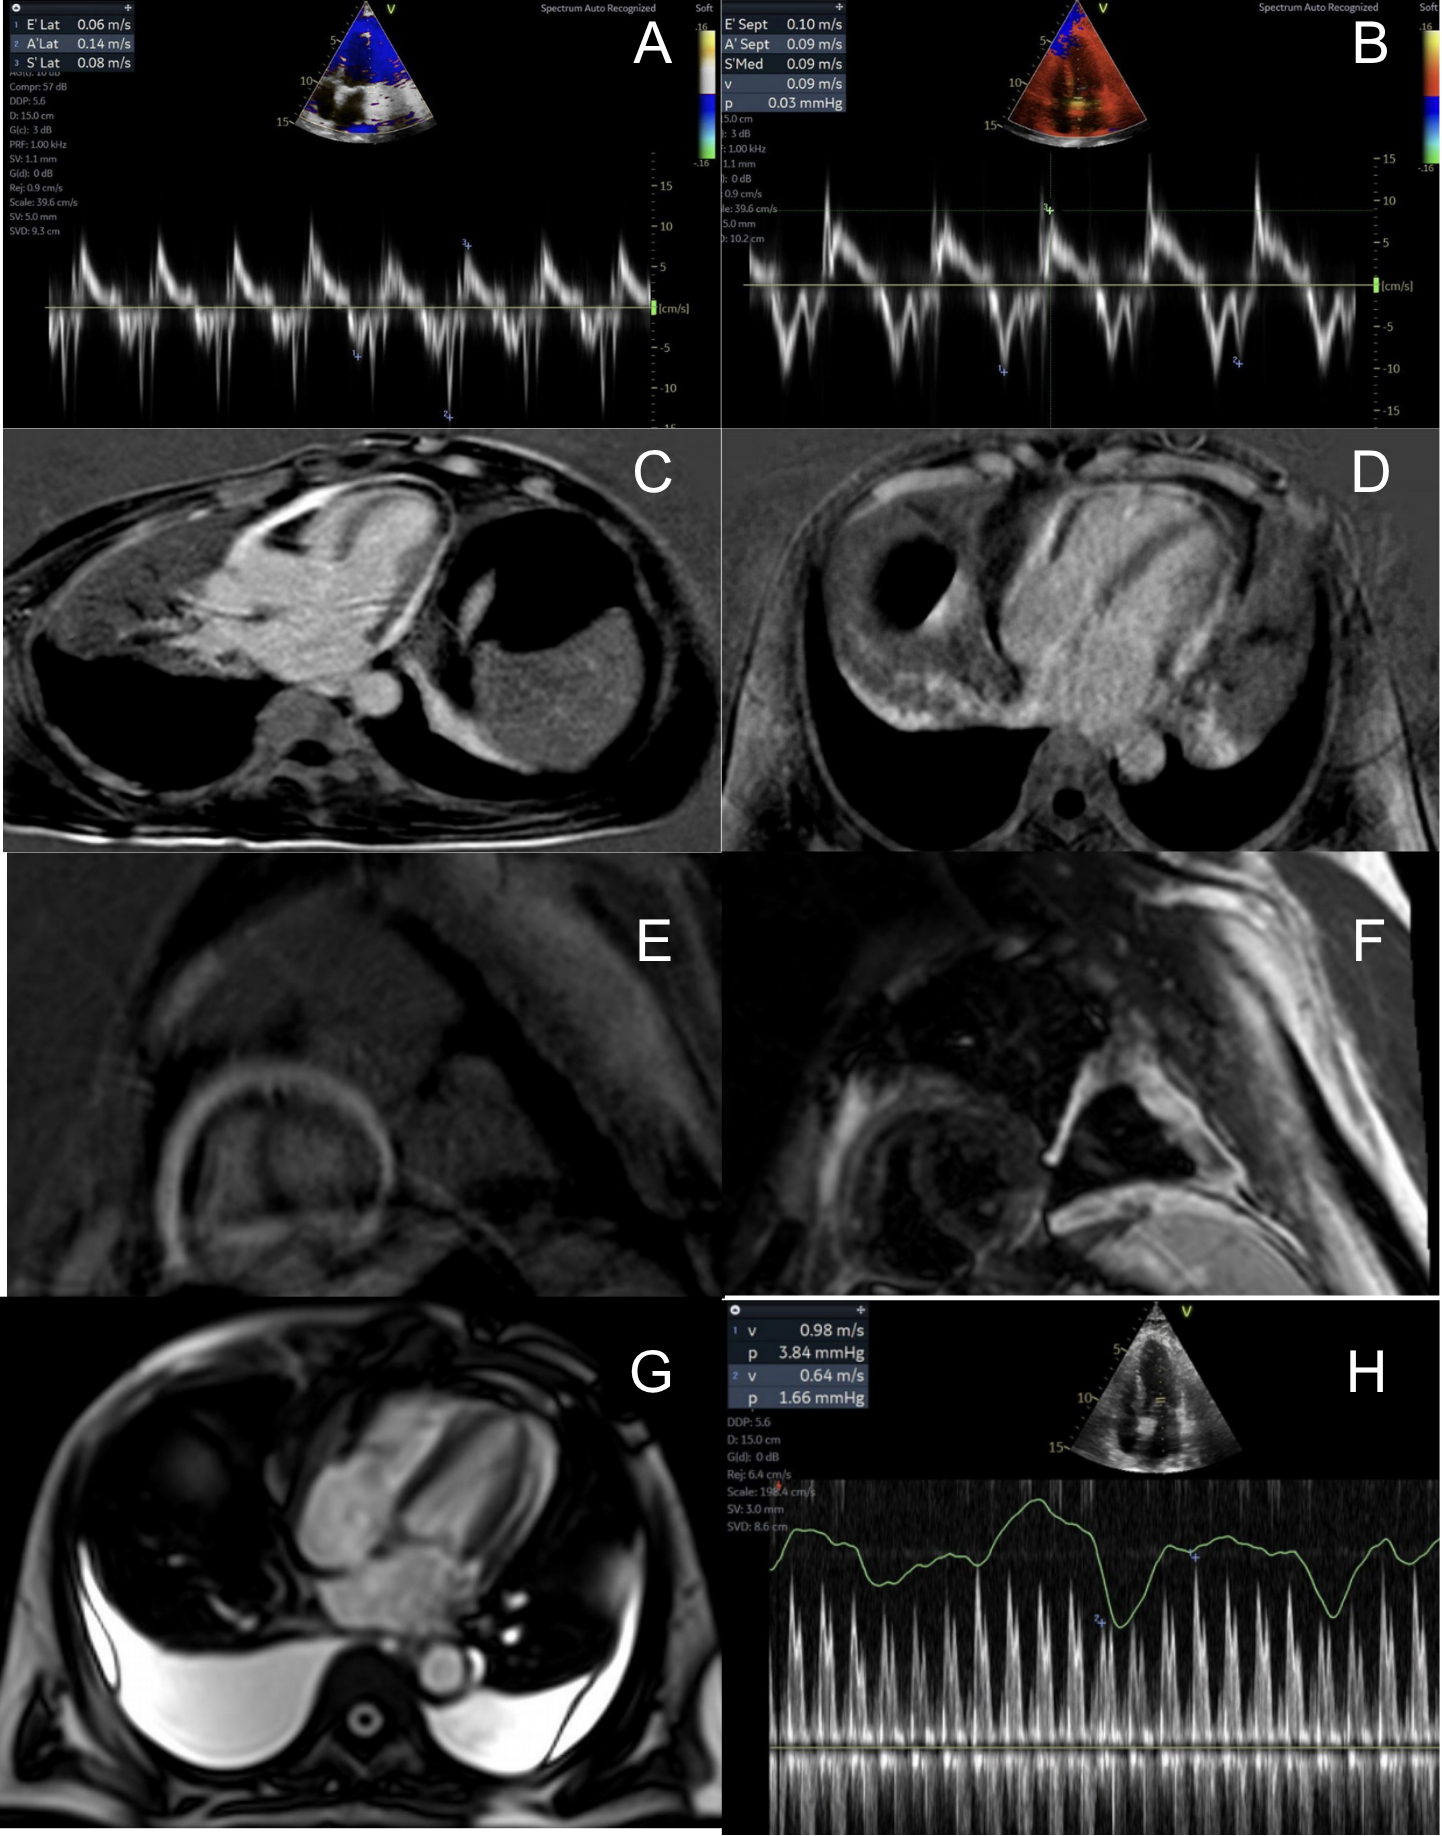

A 62-year-old man from India presented with insidious onset dyspnea, leg swelling, abdominal distension and weight gain. Physical exam revealed pedal edema, tense ascites, and Kussmaul’s sign. Initial labs showed cholestatic liver injury pattern. Imaging demonstrated bilateral pleural effusions, pericardial effusion, liver cirrhosis, and splenomegaly. Pleural fluid showed exudate, and high SAAG, low protein ascites were noted. Transthoracic echocardiogram (TTE) with Doppler showed septal bounce, annulus reversus, increased respiratory variation in mitral inflow E velocity, and atrial systolic notch on M-mode of the interventricular septum. Cardiac Magnetic Resonance imaging demonstrated patchy T2 hyperintensity with diffuse late gadolinium enhancement out of proportion to T2. Right heart catheterization (RHC) confirmed elevated and equalized diastolic pressures, confirming the diagnosis of CP. Despite the high initial concern for TB, extensive microbiological workup was negative. Absence of cavitary lung lesions, neutrophil-predominant pleural effusion, and an uncharacteristic ascitic fluid analysis for TB suggested an alternate diagnosis. Liver biopsy showed interface hepatitis, bile duct injury, and bridging fibrosis, suggesting autoimmune hepatitis/cholangitis. Serum IgG4 subclass levels returned markedly elevated at 366.4 mg/dL. Per 2020 Revised Comprehensive Diagnostic Criteria, the patient met clinical and serologic criteria for IgG4-RD. After multidisciplinary discussion regarding risks/benefits, pericardial stripping was not pursued. The patient received diuresis and paracentesis for symptom relief, and ibuprofen with colchicine for pericarditis.

IgG4-RD should remain an important diagnostic consideration in idiopathic CP, especially in the setting of multi-system involvement. In our patient, IgG4-related CP possibly co-occurred with autoimmune cholangitis. While pericardial surgery would yield maximum therapeutic benefit and histopathologic confirmation of the underlying diagnosis, our case highlights a rare form of CP caused by an infiltrative disease process.